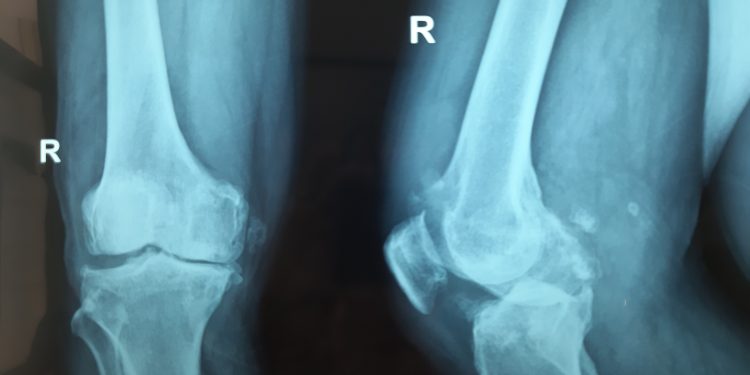

Hình khớp gối của bệnh nhân trước mổ

Ngày 10/7/2019, bệnh nhân Ngô Mạnh Đ., 71 tuổi, địa chỉ Võ Cang, Vĩnh Trung, Nha Trang được chuyển mổ với chẩn đoán Thoái hóa khớp gối 2 bên độ IV. Bệnh nhân có tiền sử đái tháo đường, trọng lượng cơ thể nặng so với chiều cao. Bệnh nhân và người nhà được BS Chính giải thích “ Lần mổ này sẽ thay khớp gối trái toàn phần. Sau khi ổn định xuất viện, tập vật lý trị liệu và phục hồi chức năng. Sau 3 tháng, thì bệnh nhân sẽ nhập viện để phẫu thuật cho chân phải.”. Bệnh nhân đã đồng ý, được chuyển mổ lúc 10h00, đến 11h30 là kết thúc và chuyển về phòng hồi sức sau mổ theo dõi.